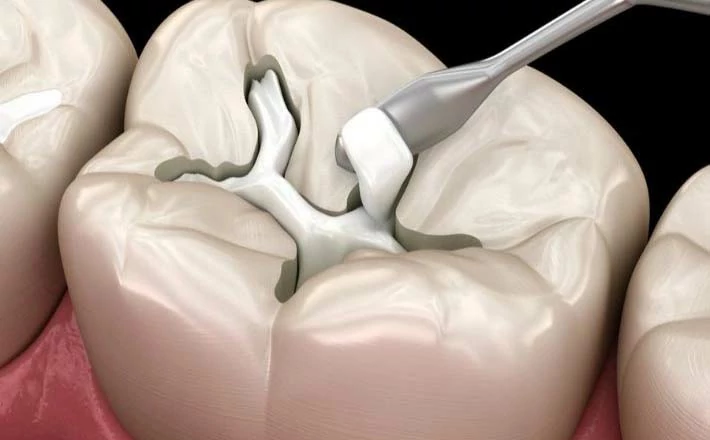

يقوم طبيب الأسنان بفحص السن المصاب، واستخدام الأدوات لتنظيفه من التسوس ومن أي رواسب جيرية، ثم يتم تشكيل التجويف ومساواته؛ حتى يصبح مناسبًا لوضع الحشوة.

الحشو المركب

تعد الحشوات المركبة من أفضل أنواع حشو الأسنان، ويتم تصنيعها من مادة الريزن وبودرة الزجاج، ويتميز بالعديد من الخصائص، فبالإضافة إلى استخدامه في حشوات الأسنان، فإنه يُستخدم في الإجراءات التجميلية، مثل الطربوش والفينير، ويمكن للحشو المركب الاندماج مع الأسنان بسهولة في وقت قصير، كما يتميز بمقاومة عالية تمكنه من تحمل المضغ وضغط الفكين.